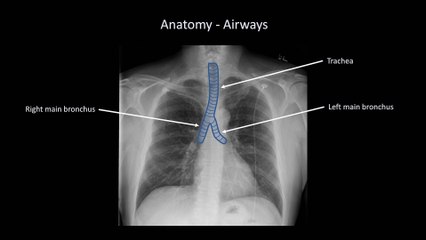

How to Interpret a Chest X-Ray (Lesson 6 - Diaphragm and Pleura)